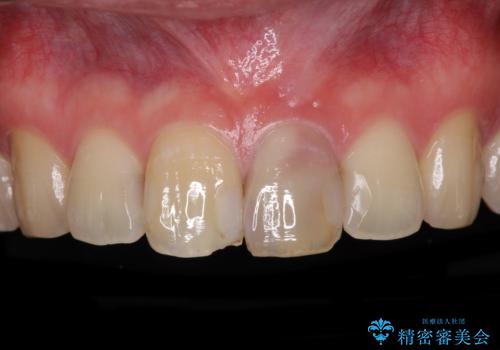

- 前歯が変色してしまったとのことで来院された患者様です。

変色が気になっていたものの痛みがなかったので看過していましたが、歯肉が腫れることが頻回となったため来院されました。

歯髄は既に壊死していたため、根管治療を行い、その後オールセラミッククラウンにて補綴することとしました。